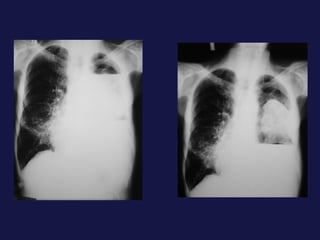

Metástasis al pulmón. El pulmón y el hígado son los mas FREC. Pueden tener varios tamaños. Imágenes nodulares, únicas o múltiples. Pueden cavitarse y calcificación.

Metástasis al pulmón.El pulmón y el hígado son los mas FREC. Pueden tener varios tamaños. Imágenes nodulares, únicas o múltiples. Pueden cavitarse y calcificación.